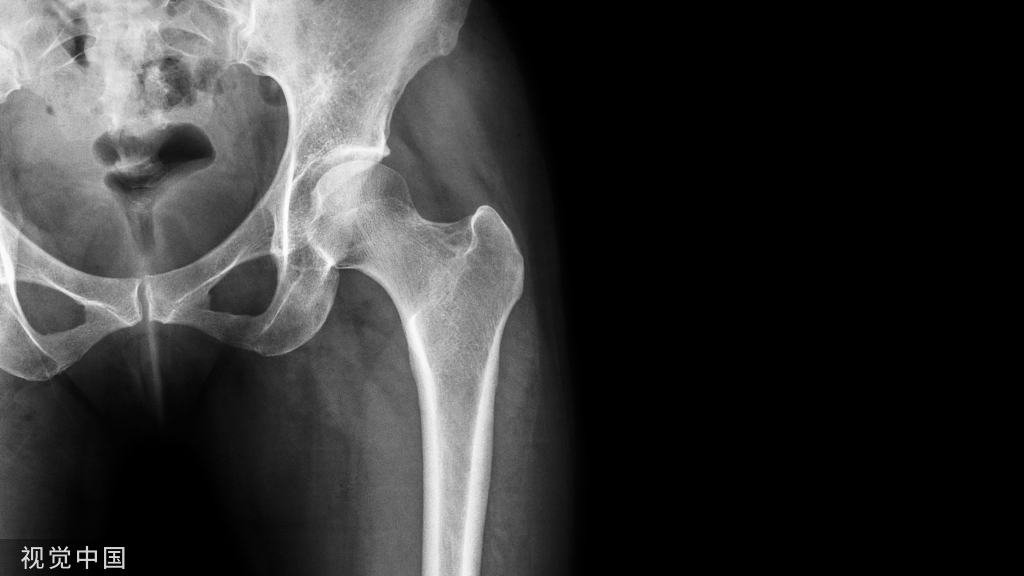

股骨粗隆骨折,术中如何正确开口?

首先,我们要在大粗隆近端做一个2~3公分的小切口,建立一个良好的软组织通道。对年龄比较大的、骨质比较疏松的病人,为了减少手术时间,可采用开口器直接开口,直接插钉的方法。开口的同时要特别注意,手指先摸到大转子顶点偏内侧,然后,开口去顺着手指方向插入,开口器一定要紧贴着身体轴线。

开口器顺着髓腔方向旋转地插入,用力的时候因为内侧皮质比较硬,外侧的比较软。所以,开口用力的方向一定是偏内向髓腔方向,大部分情况下都能一次成功。

透视下定位比较准确以后就可以插钉。当然,有的医生经验不是很丰富,手摸心会还不能达到很高的层次。那么,建议还是多透几下,正位、侧位都要多透几下。然后,可以根据髓腔的方向不断地调整,以达到最佳的开口。

也有一些病人骨折线正好位于开口区,或者年纪比较轻,骨头质量比较好,不能通过直接开口的方法插钉,这时候需要克氏针加导针定位的方法,先精确地置入正确位置的导针,然后,再以导针为中心,进一步扩髓以扩大开口。

要特别强调的是,开口一定要充分。否则,很容易造成插钉时骨折的移位。但实际上,由于操作空间的限制以及该处皮质内紧外松的特点,临床上经常会发现扩髓时内侧比较坚硬的皮质,经常会阻挡并且推顶扩髓钻向更松软的大粗隆侧移位,造成进针点外移这种现象。